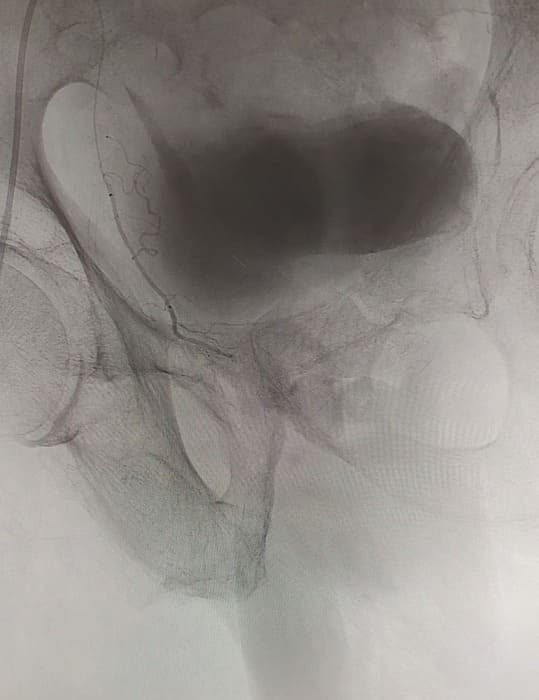

Зазвичай люди літнього віку мають вражені атеросклерозом та звивисті, внаслідок гіпертонічної хвороби судини. Цей випадок не був виключенням, тому нам довелося докласти максимум зусиль, використати високотехнологічне обладнання та інструменти, щоб віднайти цільові судини. На диво, незважаючи на попередню операцію, судинний малюнок рецидивної простати збігався з тим який буває у не оперованих пацієнтів. Тому нам вдалося їх чітко визначити з обох сторін та заповнити емболами. Це доволі кропітка праця, адже щоб викликати ішемію, необхідно поступово виключити кровоплин в усій тканині залози. Полегшувало операцію лише відсутність перетоків артерій на сусідні органи. Це дозволило нам безпечно емболізувати, не боячись негативних наслідків та ускладненнь.

Операція була виконана 28.05.2021. під місцевою анестезією, доступом через прокол в правій стегновій артерії. Вже на протязі тижня зменшилась кількість походів в туалет по маленькому (вночі до 1 разу), полегшилось сечовиділення та покращилось самопочуття хворого.